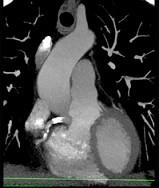

下面一组图像应考虑为 ( )A、左前降支钙化B、左旋支钙化C、正常的左前降支D、右侧冠状动脉钙化E、正常的右侧冠状动脉

问题 下面一组图像应考虑为 ( )

选项 A、左前降支钙化 B、左旋支钙化 C、正常的左前降支 D、右侧冠状动脉钙化 E、正常的右侧冠状动脉

答案 D